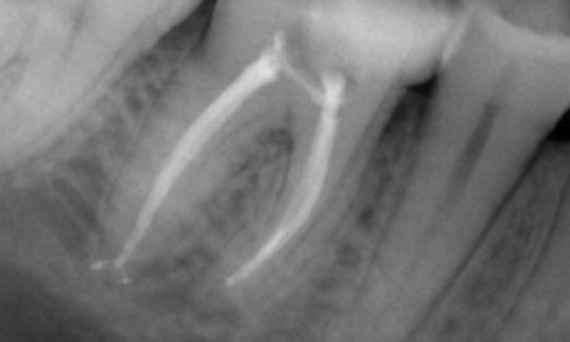

Avant : Radiotransparence périapicale associée principalement à la racine distale et à la perte de la lamina dura sur la racine mésiale.

Après : TruNatomy a été choisi dans ce cas pour permettre une approche adaptée aux caries et une préservation de la dentine péricervicale, en particulier au niveau de l’aspect mésial où la restauration de la dent était minimale.